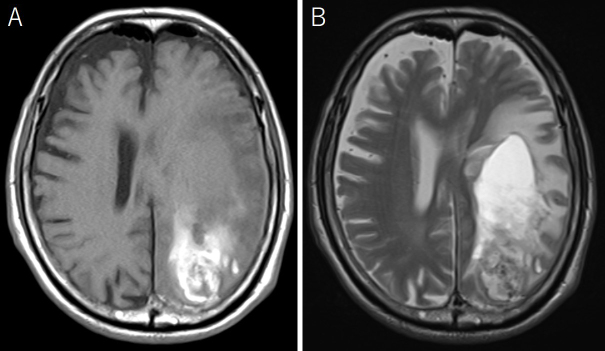

Porencephalic cysts are very rare in adults. Herein, we present a case of an 88-year-old man with a symptomatic expanding porencephalic cyst after intracerebral hematoma evacuation. He was admitted because of disturbed consciousness and right hemiparesis. A computed tomography (CT) showed a large subcortical hematoma in the left parietal lobe. Hematoma evacuation was performed, his consciousness level improved but gradually deteriorated. Follow-up CT revealed a new cystic lesion with perifocal edema at the hematoma site, with progressive expansion of the cyst. Cyst drainage and -peritoneal shunt placement were performed on postoperative day 14; consequently, his symptoms improved. Considerably, a porencephalic cyst have developed because the cerebrospinal fluid flowed into the closed hematoma cavity from the ventricle owing to the osmotic pressure difference between the ventricle and the hematoma cavity.